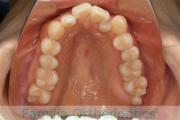

No.23V-061

- 主な症状:

- 叢生

- その他の症状:

- 上下顎前突

- 年齢:

- 23歳

- 性別:

- 女性

- 抜歯部位

- 上:

- 44

- 下:

- 主な使用装置:

- FEA 022

- 治療にかかった費用:

- 88万円

でこぼこを綺麗に並べたいということで来院されました。上下左右から小臼歯を抜歯して、マルチブラケット法を2年半、30回程度通院していただいて行いました。

かなり強い叢生(でこぼこ、凹凸、ガタガタ)のため、保定をしっかりしないと後戻りのリスクが高いケースといえます。